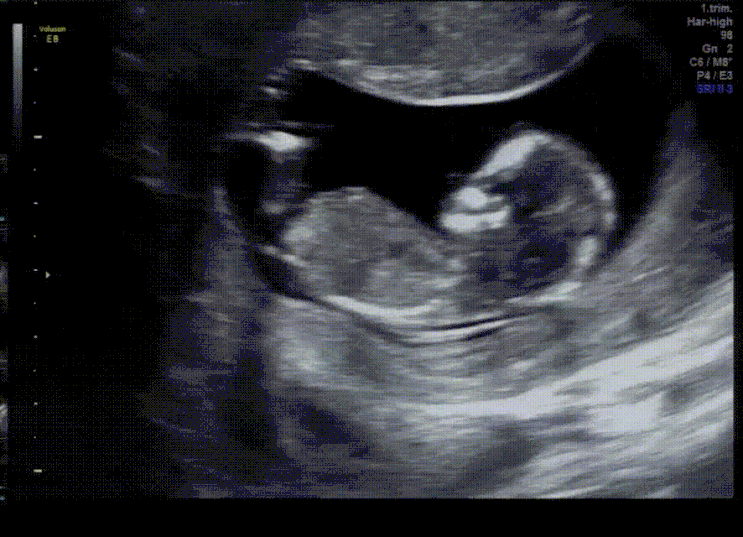

[나의 임신일기] #2 도담도담, 튼튼하게 잘 크는중

임신 6주 - 임신 14주 초산모의 임신일기 #2 도담도담, 튼튼하게 잘 크는중 임신을 알고나서 여러 태명중에...